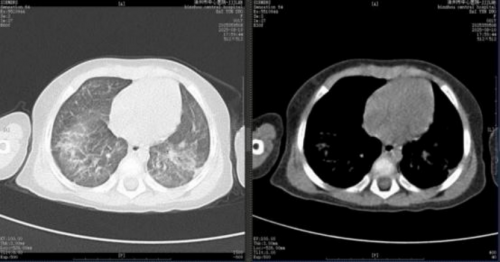

4.影像学持续好转:2025 年 6 月 24 日复查胸部 CT(见图 6),结果显示肺部病变较前继续好转。8 月 10 日复查胸部 CT,显示双肺病变已明显吸收(见图7)。

图 7

通过上述综合干预,患儿病情逐步迎来转机。动态影像学监测清晰展现了肺部病变的持续改善:从5 月 28 日 CT 显示的“双肺炎性病变较前(5-14)有吸收”,到 6 月 24 日“较前好转 ”,直至8 月 10 日复查 CT 见病变明显吸收,客观印证了治疗的有效性。在此过程中,患儿呼吸功能显著恢复,成功脱离有创通气,序贯经鼻高流量氧疗及鼻导管吸氧,最终于8 月 13 日生命体征平稳出院。本例救治经验表明,对于传统治疗方案反应不佳的儿童重症肺炎及 ARDS,在综合支持基础上,早期并分阶段应用西维来司他钠,能有效改善氧合、减轻肺损伤,可能成为避免肺移植、改善预后的关键决策。其疗效与本例中观察到的 PaO₂/FiO₂比值提升及影像学改善相符,为共识的临床实践提供了有力佐证,但其在儿童群体的广泛应用仍需更多研究进一步验证。